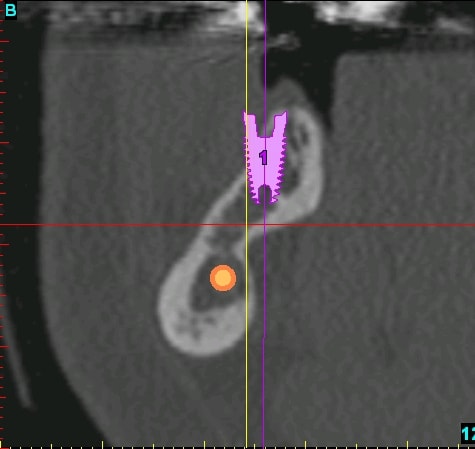

D1 absence de total de trabicules (selon Mis Jordy) donc entre les foramens mentonnier, partie basse et linguale de la mandibule

voilà pour compléter...

pano et les coupes pour les 2 futurs implants...

ce qui me posait problème, c'est l'inclinaison et la forme de la branche horizontale dans cette zone rendant l'implantation simultanée extrêmement délicate...pour ne pas dire risquée...

Comme quoi la pano veux rien dire ! La forme de la crête est môche !